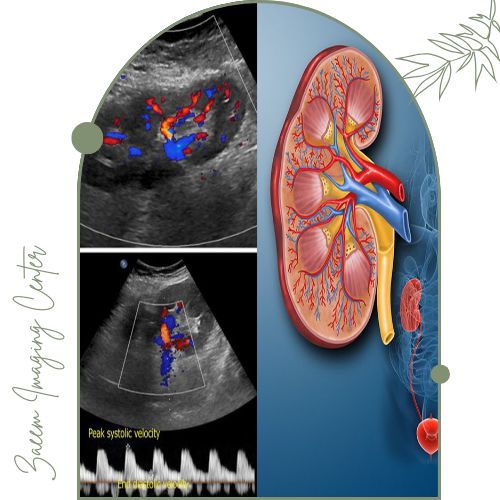

سونوگرافی کالر داپلر کلیه یک روش پیشرفته تصویربرداری غیرتهاجمی است که برای بررسی دقیق‌تر سلامت کلیه‌ها و عروق خونی آن‌ها به کار می‌رود. آنچه این روش را از سونوگرافی معمولی متمایز می‌کند استفاده از فناوری «داپلر رنگی» است. در این تکنیک دستگاه قادر است حرکت گلبول‌های خون در رگ‌های کلیه را ردیابی کرده و سرعت و جهت جریان خون را در قالب رنگ‌های مختلف (معمولاً قرمز و آبی) نمایش دهد. این کدگذاری رنگی به پزشک اجازه می‌دهد تا مسیر و شدت جریان خون را به راحتی مشاهده کند و هرگونه اختلال مانند تنگی عروق یا انسداد را به سرعت تشخیص دهد.

تفسیر نتایج بر اساس معیارهای مشخصی انجام می‌شود که عمدتاً به سرعت جریان خون، الگوی عبور خون از شریان‌ها و شاخص مقاومت عروقی وابسته است.

در حالت طبیعی جریان خون در شریان‌های کلیوی یکنواخت و سرعت آن متناسب با وضعیت کلیه است.

اگر تنگی یا انسداد وجود داشته باشد، معمولاً سرعت خون در نقطه خاصی افزایش یافته و شاخص مقاومت تغییر می‌کند.

همچنین رادیولوژیست با مشاهده رنگ‌های خاص در تصویر می‌تواند اختلالات جریان، وجود لخته یا آسیب عروقی را تشخیص دهد.